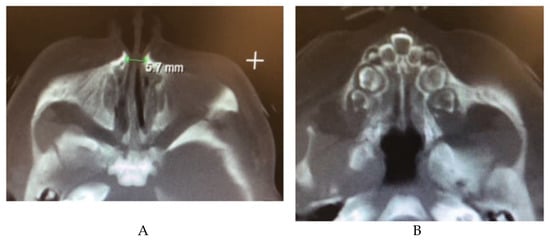

2.12.1. Congenital Nasal Pyriform Aperture Stenosis